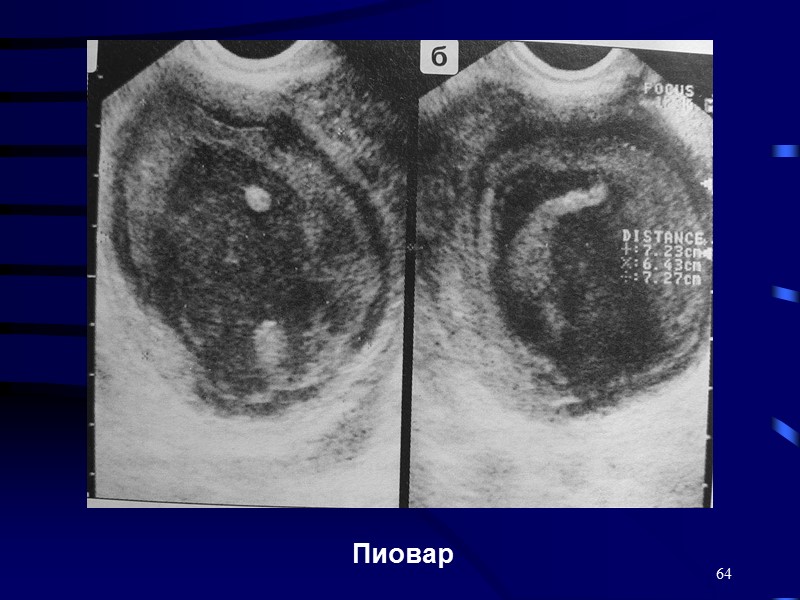

КТ диагностика тубоовариального абсцесса: Подходы и изображения

Раздел: Объективный взгляд